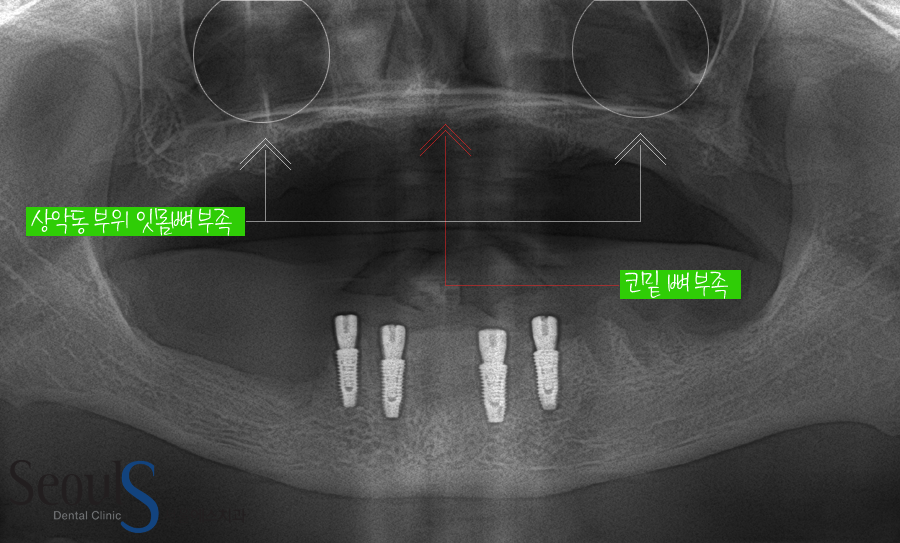

X-ray 사진을 보시면

윗니의 잇몸뼈 상태를 확인할 수 있는 X-ray 사진입니다

윗니는 대부분 잇몸뼈가 많이 부족한 상황입니다

어금니 부분은 아무리 잇몸뼈가 부족해도 상악동 거상술 잇몸뼈이식으로 임플란트 식립이 가능한데

코밑에 잇몸뼈가 부족한 경우..

잇몸뼈이식의 난도가 높아서 이 부분이 고민되는 상황이었습니다

윗니 상악동 거상술 잇몸뼈이식과 함께 임플란트 6개를 식립한 모습입니다

앞에서도 말씀드렸는데

코밑 부분에 잇몸뼈이식은 난이도가 높고 부작용이 생길 수 있기 때문에 고민이었는데….

현재 식립 된 6개의 임플란트로 보철물을 결합하기에는

보철물 앞니 부분이 길어지기 때문에 만족할만한 결과를 얻기 힘든 상황입니다

CT 정밀 진단 후 최적의 위치를 찾아 뼈이식을 시행했습니다

코 부위 뼈이식의 경우 난이도가 높고 부작용이 생길 수 있는 수술이지만

정확한 진단 후 수술 했기 때문에 성공적으로 수술을 마칠 수 있었습니다